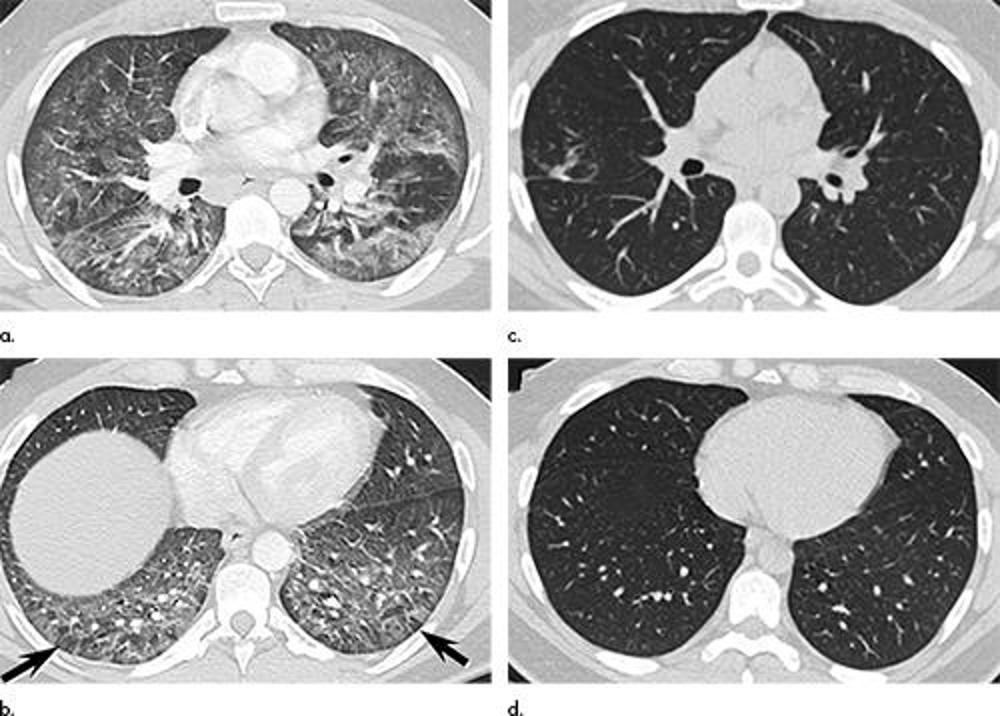

Figure 5. Images in a 39-year-old man with respiratory failure hospitalized for 10 days with an electronic cigarette or vaping product use–associated lung injury manifesting as an acute lung injury pattern at CT with some CT features suggesting a hypersensitivity pattern. (a, b) Axial enhanced CT images through the (a) mid and (b) lower lungs at presentation show multifocal areas of ground-glass opacity with prominent lobular low attenuation in the bases (arrows) suggesting small airway obstruction in addition to the ground-glass opacity. (c, d) Axial unenhanced CT images through the (c) mid and (d) lower lungs obtained 64 days after presentation show complete clearing of lung parenchymal abnormalities. Right middle lobe opacity (c) reflects site of surgical lung biopsy, which showed acute lung injury with organization, but no granulomas or other features typical of hypersensitivity pneumonitis.